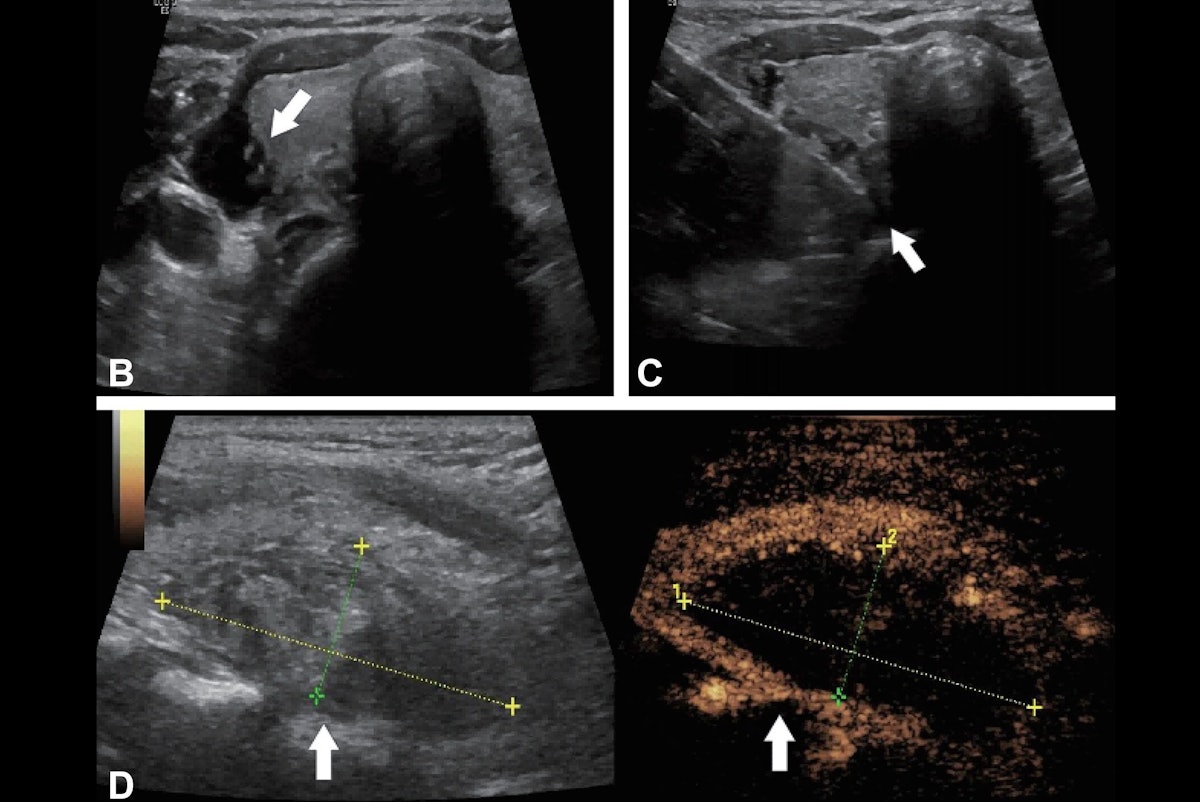

Microwave and radiofrequency ablation are safe and effective alternatives to surgery in older participants with hyperparathyroidism, according to a study published October 28 in Radiology.

The finding is from a trial of the procedures in 153…